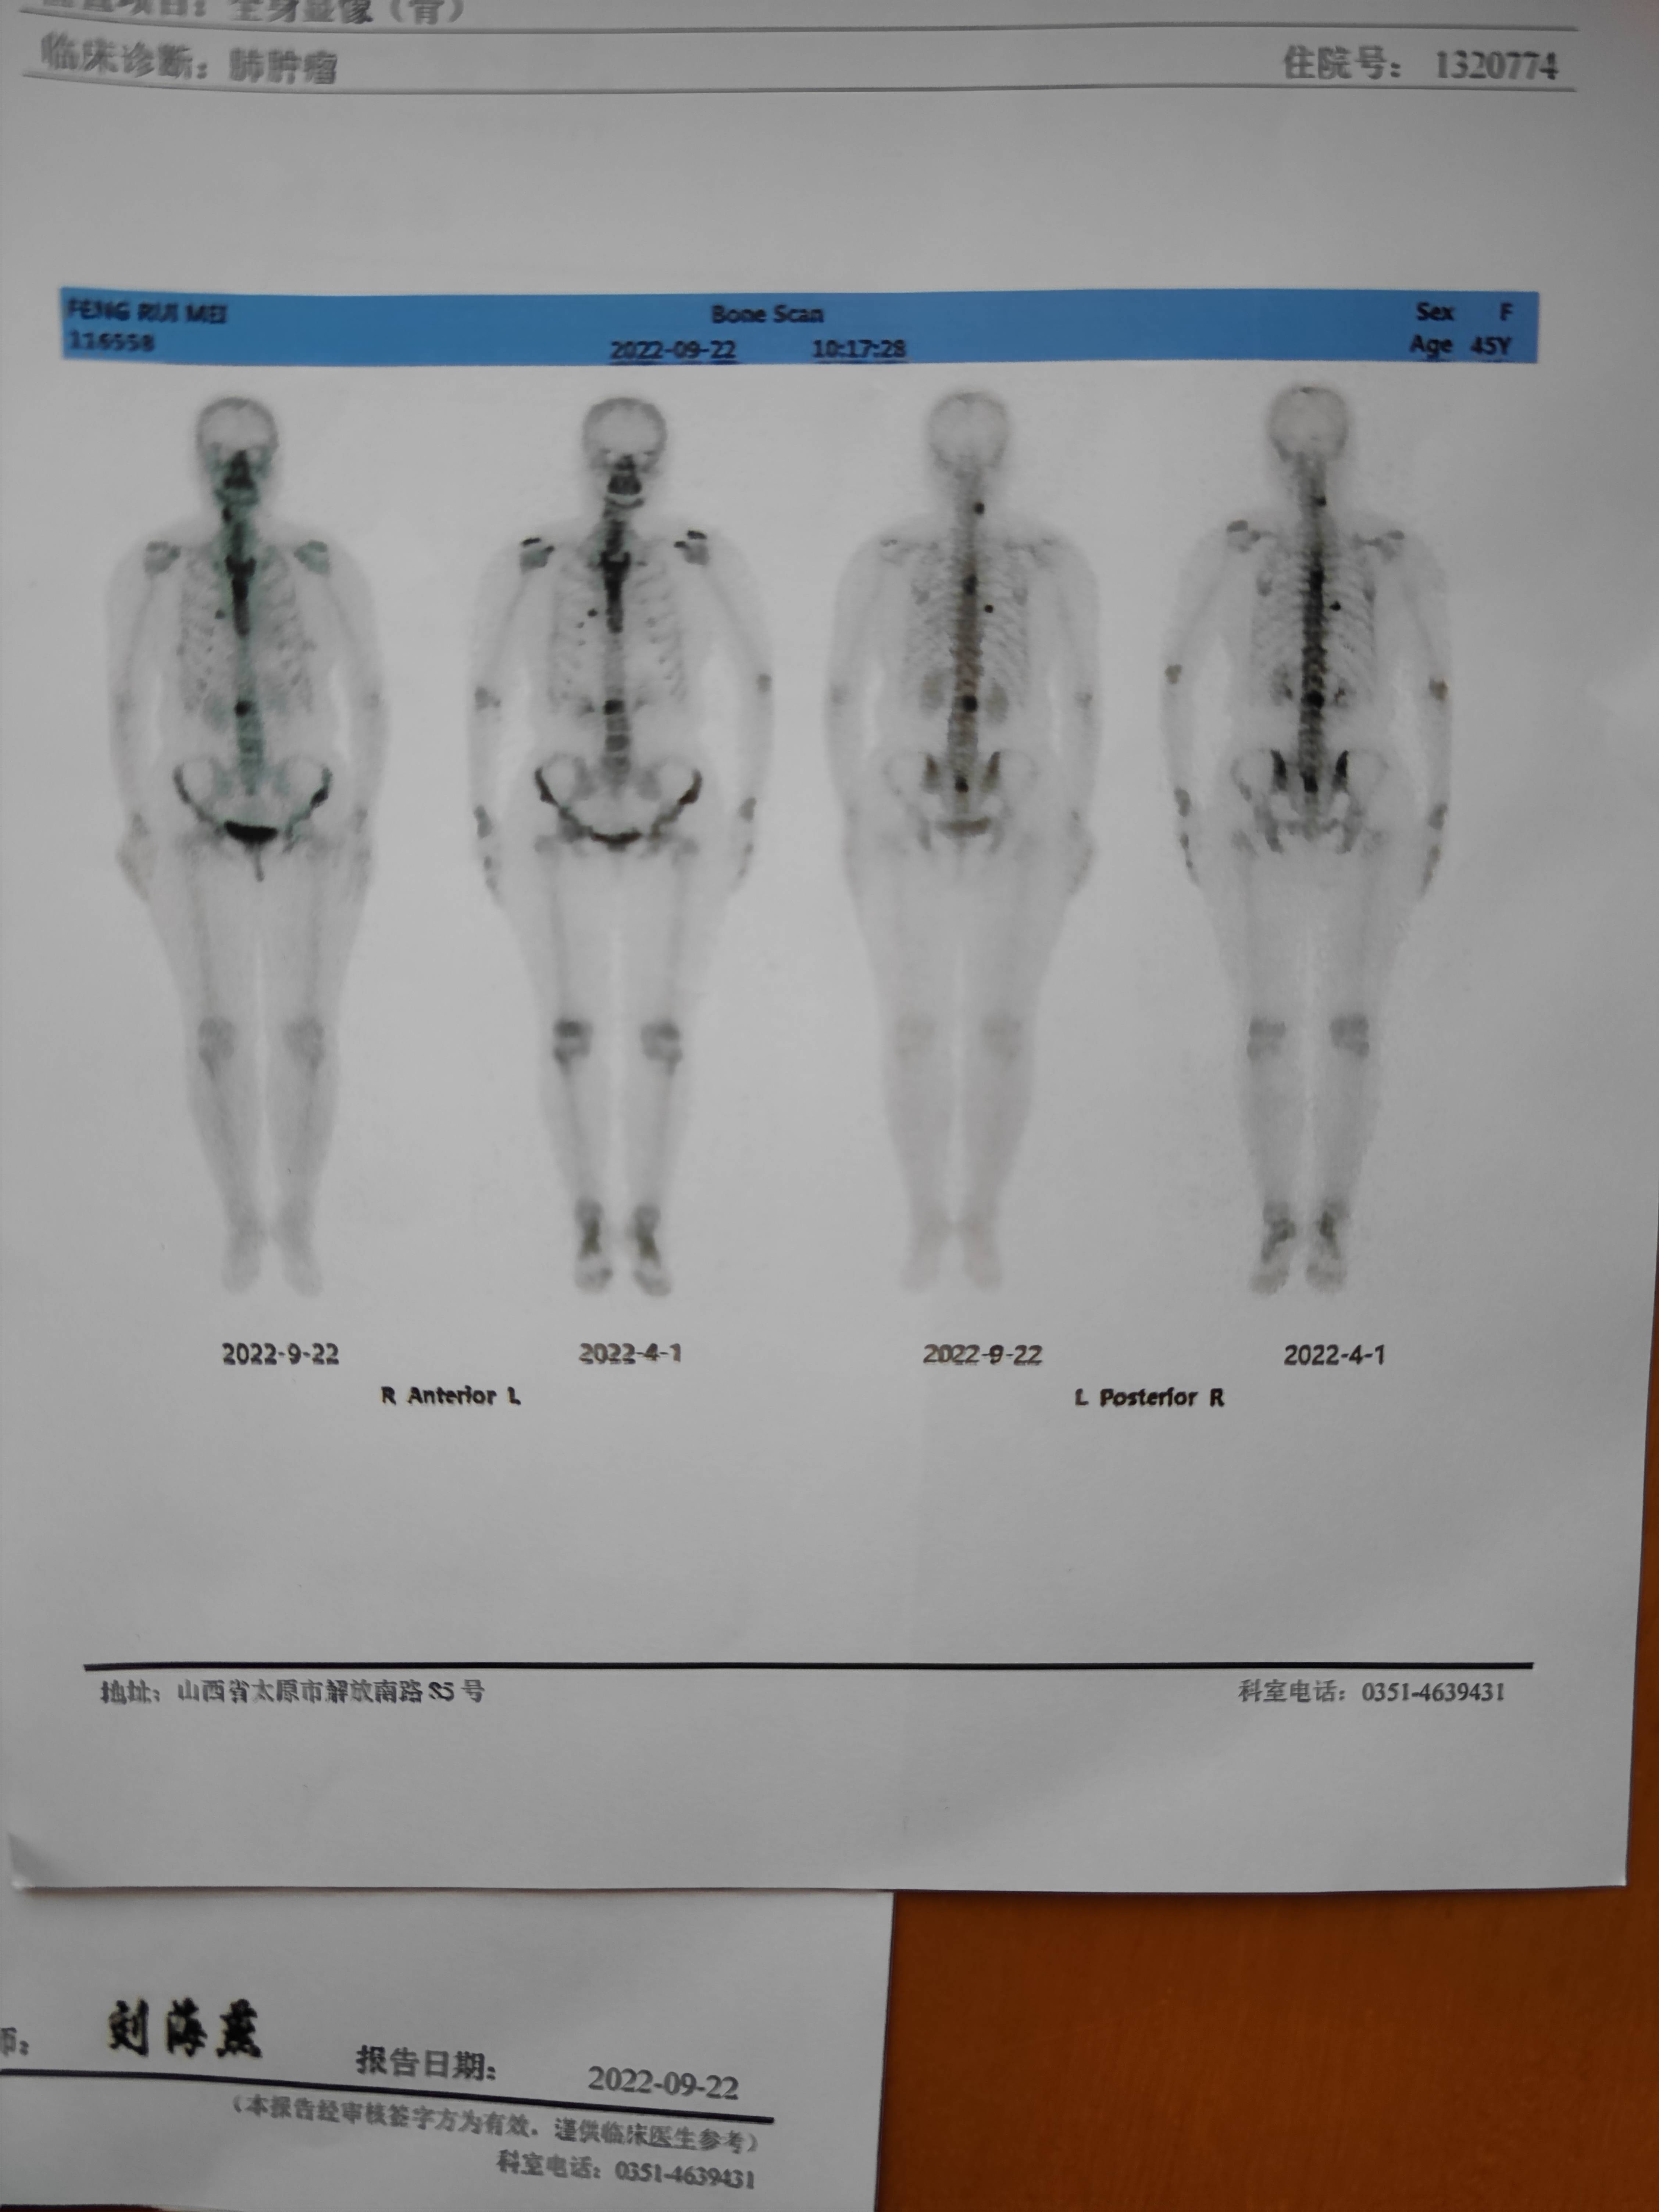

之前脑部肿瘤是0.4cm,此次复查结果让人开心,显示看不见了,骨扫描提示无明显变化。但是让人忧愁的主要是肺部病灶的变化,提示肺部主病灶增大0.1cm,无明显变化,余发小结节略增大。但是报告并未给出这个略增大的具体情况。

另外每次骨扫描病灶都没有变化,这种情况是必须放疗吗,化疗对病灶治疗不大吗?目前除了腰部在活动后有些不适,其余部位没有异常感觉。根据骨扫描的结果需要做哪些治疗吗?